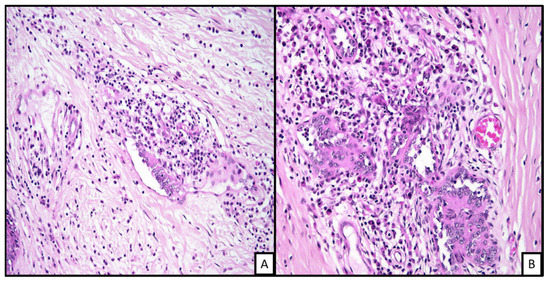

3.4.4. Histologic Features

3.4.5. Ancillary Testing and Immunohistochemical Stains